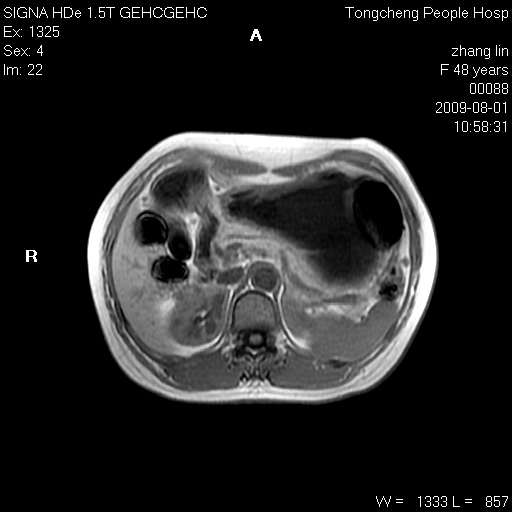

女,48岁。健康体检,彩超发现右肾占位性病变。平素健康。

临床诊断:右肾占位性病变,性质待定(囊肿?肿瘤?)。

上中腹部mr平扫+增强扫描,图像如下:

右肾上极见一类圆形病灶,t1wi呈等信号t2wi呈等高混杂信号,三期增强无强化,边界清---考虑囊肿出血。

同反相位均表现为等信号,病变无强化,考虑含蛋白的囊肿可能,弥散加权相或许有些帮助,

慢性胆囊炎